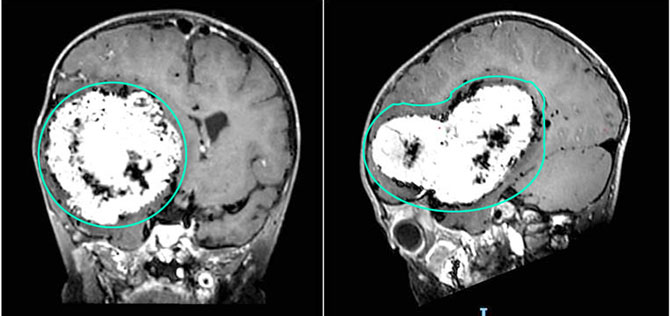

近日,广东省人民医院神经外科周东教授收治了一名辗转多家医院后来到省医就诊的脑膜瘤患者小初(化名)。小初今年两岁,最近总是精神萎靡、走路不稳,手脚的运动能力也比较差,并伴有左侧肢体活动减少。家长表示孩子近期反应明显迟钝,与同龄儿童相比行为异常,还反复呕吐。经头部MR增强检查,发现右侧大脑半球存在一巨大颅内占位,肿瘤直径约10厘米,严重压迫周围正常脑组织,病情十分危急。为了挽救这位小患者的生命,广东省人民医院周东主任团队立即决定实施手术,以期彻底切除肿瘤。

术前影像资料可见右侧大脑半球巨大肿瘤占位。